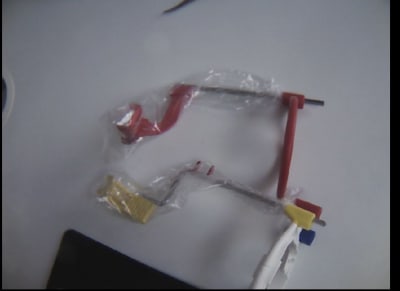

Les super bite de kerr, pas la moindre trace d'usure après une année de stérilisation. Et très simple d'usage et peu encombrant en bouche

Faudrait que je remette la main dessus j'avais pas aimé les kerr . Les xtp par contre sont pas mal tu fais des radios dans tous les sens . Rétro coronaires verticales et rétro alvéolaires verticales avec leur seul tip de mordu pour rétro coronaires vertical.